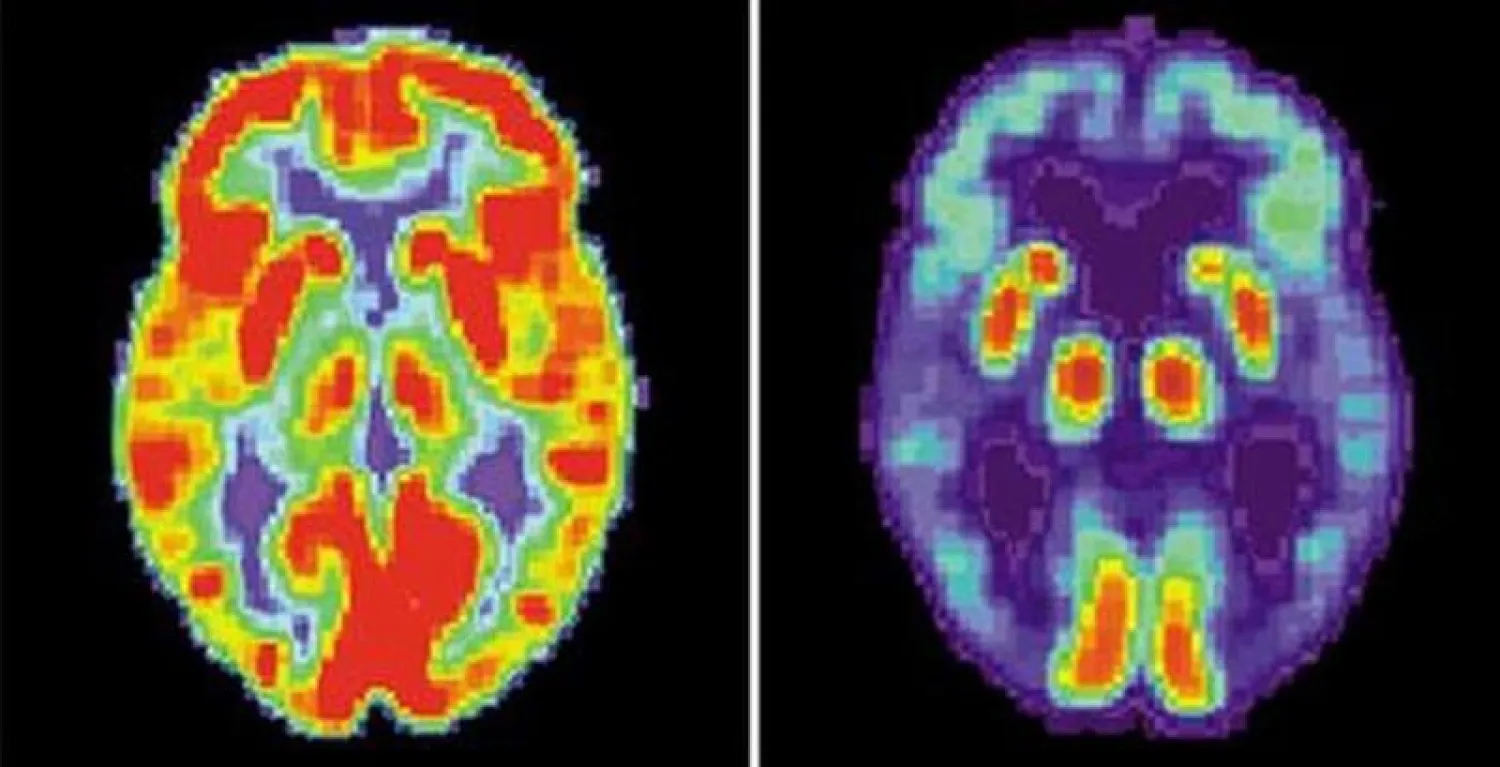

قياس نشاط المخ هو أساس النظام المطوّر (أرشيفية - رويترز)